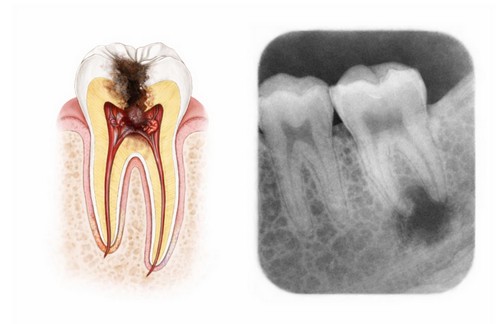

In order to understand Endodontic treatment, it helps to know something about the anatomy of a tooth. Teeth have several layers. The outside layer of the tooth is composed of a hard layer called Enamel. Enamel is supported by an inner layer called Dentin, which has at its center a soft tissue known as the Pulp.

The pulp contains blood vessels, nerves, and connective tissue that are responsible for forming the surrounding Dentin and Enamel during tooth development. The pulp receives its nourishment supply from vessels which enter the end of the root.  Although the pulp is important during development of the tooth, it is not necessary for function of the tooth. The tooth continues to be nourished by the tissues surrounding it even after the pulp has been removed.

Endodontic treatment is necessary when the pulp becomes inflamed or infected. The most common reasons for inflammation or infection are deep cavities (caries), repeated dental procedures, cracks or chips. Trauma can also cause inflammation and often shows up as discoloration of the tooth.  If pulp inflammation or infection is left untreated, it can cause pain or lead to an abscess (infection).

Indications for treatment include prolonged sensitivity to heat or cold, discoloration of the tooth, swelling or tenderness of the tooth or adjacent gums. Sometimes there are no symptoms.